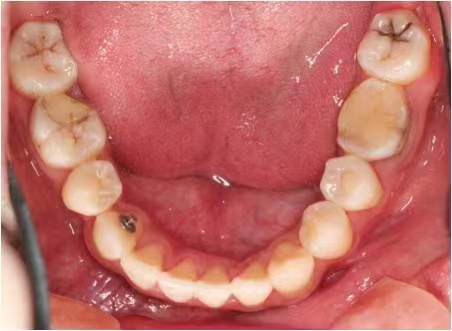

情况:不接受外科手术,在当地做了1年半的矫治,遇到困难无法进行。由外地正畸同行推荐来上海寻求非手术矫治的二手病例。武广增老师接收时的错合畸形情况,呈现严重的骨性反合偏合及侧方开合(图1-图10)。由于推荐其去口腔医院接受正颌外科手术遭到拒绝,武广增老师通过专业的检查、分析,制定一套详细的治疗计划,采用了磨牙推进器技术、武式辅弓技术等特色正畸手段获得明显效果(图2-1~图2-9)。治疗结束后也拍摄了相关照片(图3-1~图3-9)。

矫治前

图6

图7

图8

图9

图10